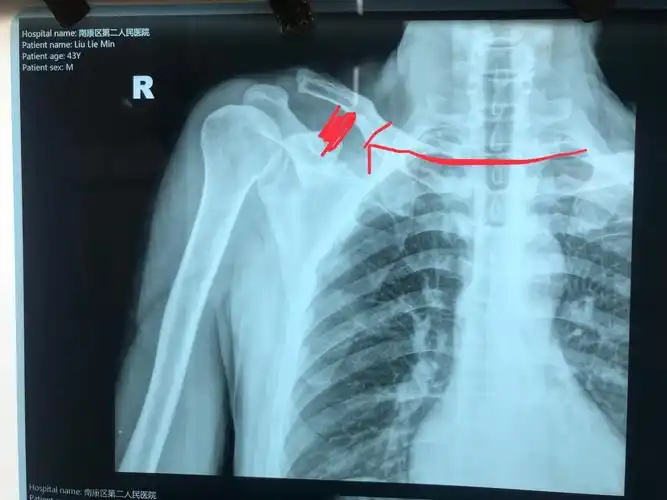

术前可见右肩关节脱位,喙突与锁骨间隙增大.